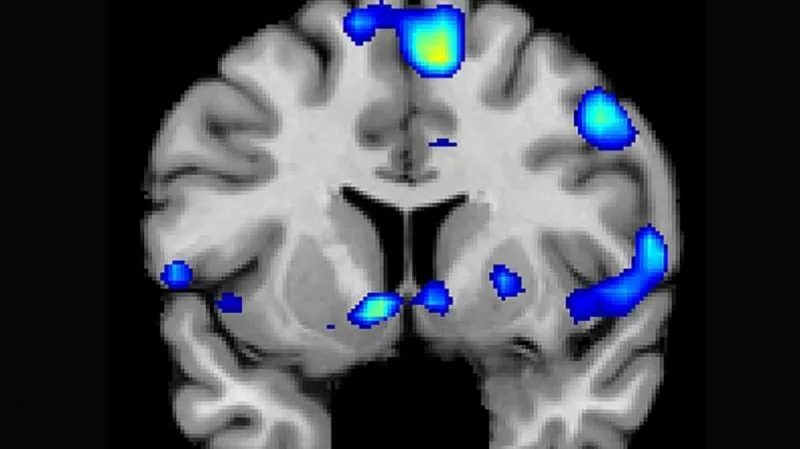

Hoekzemaová a její tým studují změny mozku u žen ve Španělsku pomocí magnetické resonance. Testovali mozky 25 žen, které ještě nikdy neměly děti předtím, než otěhotněly – a pak znovu až do několika měsíců po porodu. Také skenovali mozky otců, a to ve stejných intervalech jako ženy; v kontrolní skupině bylo 17 mužů a 20 žen, kteří během výzkumu neměli děti. Pomocí počítačové analýzy pak data analyzovali, aby zaznamenali rozdíl v šedé hmotě mozkové.

Jak je vidět, skupina osob, na níž výzkum probíhal, je poměrně malá, vynahrazuje to komplexnost výzkumu. Jediná skupina, u níž se projevoval dlouhodobý úbytek šedé hmoty, byly právě matky. Úbytek se projevil nejvíce v oblastech mozku, které jsou zapojené do řešení sociálních problémů – jako je například odhadování přání a záměrů ostatních podle jejich mimiky a chování. Objem ztratila také oblast hipokampu, která je zodpovědná za paměť a vzpomínky. Současně vědci zaznamenali, že výsledky matek v testech, které měří míru pozornosti vůči jejich dítěti, se daly předpovědět podle toho, o kolik mozkové hmoty přišly.

Vědci sledovali mozek on-line pomocí magnetické resonance, kdy se matky dívaly na fotografie jejich dětí a snímky cizích potomků. Mnoho oblastí mozku, které přišly o šedou hmotu během těhotenství, na fotografie vlastních dětí reagovaly nejsilnější aktivitou – zato na ostatní kojence nereagovaly téměř vůbec.

O dva roky později se vrátilo 11 matek z 25 (tedy ty, které znovu neotěhotněly) na scanování znovu. Výsledky byly u všech totožné: šedá hmota mozková se už neobnovila, s výjimkou hipokampu, jenž se naopak vrátil do původního objemu. Tyto změny byly natolik pravidelné, že počítačový algoritmus pak podle mozkového scanu dokázal předpovídat se 100procentní úspěšností, zda už žena byla těhotná.